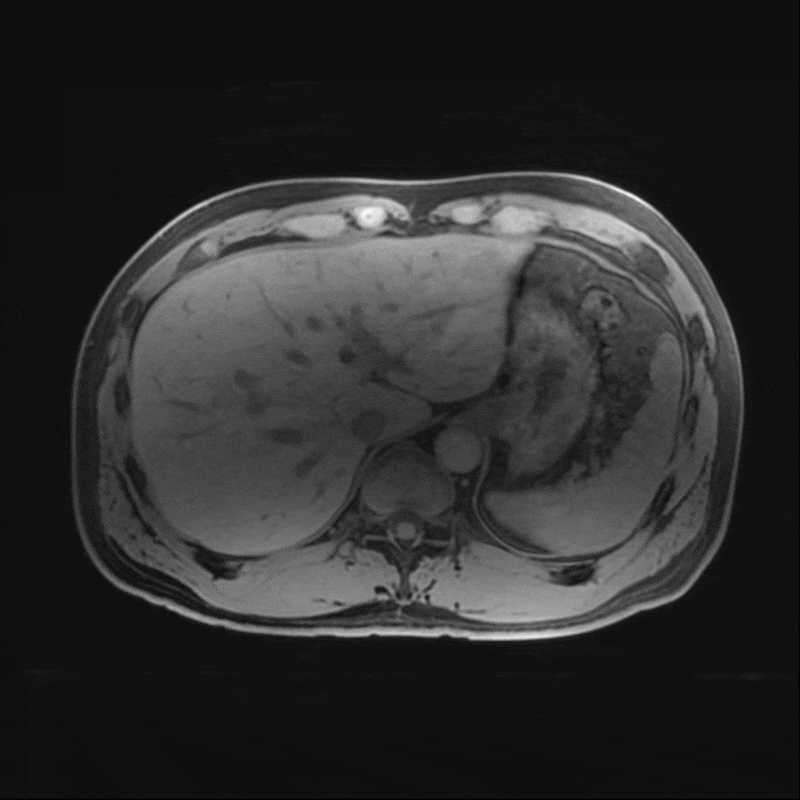

To accurately track the progression of ADPKD, an MRI of the patient’s abdomen was performed, utilizing a gadolinium-based IV contrast agent. This contrast enhances the visibility of kidney cysts and aids in clearly delineating their boundaries, which assists in creating accurate measurements and identification of kidney structures. A radiologic technologist then carefully segmented both kidneys, isolating them from other anatomical structures in the images. Isolating the kidney allowed the technologist to calculate their volumes in cubic centimeters (cm³).

Figure B: Segmentation performed on both kidneys, isolating them from the rest of the patient’s anatomy.